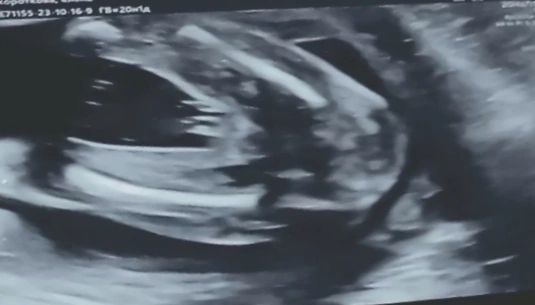

Узи. Пол ребёнка

Очевидно, девочка)

а какие тут могут быть сомнения?) вроде очень четкое фото)

Тут девочка без сомнений.